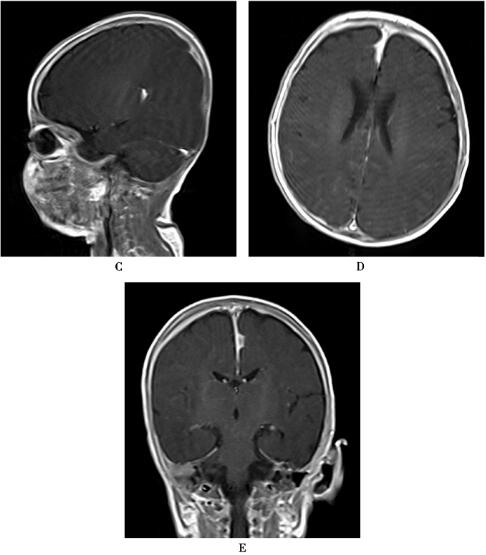

图1 特发性肥厚性硬脑膜炎

平扫灰白质界限欠清晰,增强后颅内硬脑膜明显广泛增厚强化,颅脑实质内未见明显异常强化灶

特发性肥厚性硬脑膜炎是一种少见的中枢神经系统慢性无菌性炎性疾病,病理上以颅内硬脑膜弥漫性增厚和纤维性炎症过程为特征,增强后主要表现为沿颅顶或颅底之颅板下方以及小脑幕、大脑镰分布的硬脑膜局部或弥散性强化影,特发性肥厚性硬脑膜炎的病因及发病机制尚未明确。脑膜活检是诊断特发性肥厚性硬脑膜炎的确诊手段。